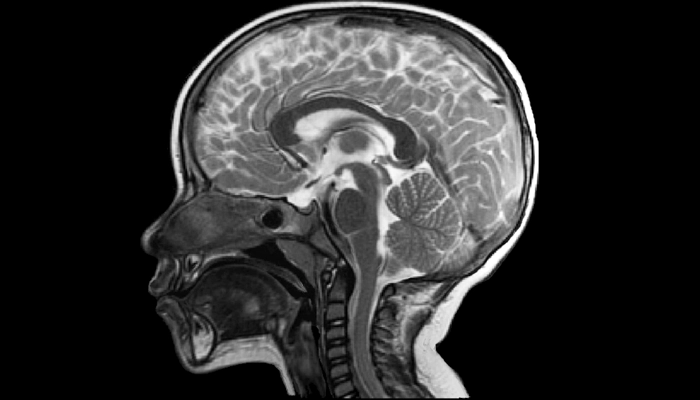

5.3. Chẩn đoán hình ảnh não (MRI não)

Mục tiêu: tìm nguyên nhân cấu trúc hoặc tổn thương não gây co thắt.

MRI não là phương tiện ưu tiên (độ nhạy cao hơn CT).

Có thể phát hiện:

Dị tật vỏ não (cortical dysplasia, loạn sản ống thần kinh).

Bệnh não thiếu oxy, chảy máu, nhiễm trùng, hoặc u não.

Bệnh di truyền, chuyển hóa (nếu không tìm thấy tổn thương rõ ràng).

Chẩn đoán hội chứng West dựa vào sự kết hợp của lâm sàng, điện não đồ (EEG) và chẩn đoán hình ảnh thần kinh